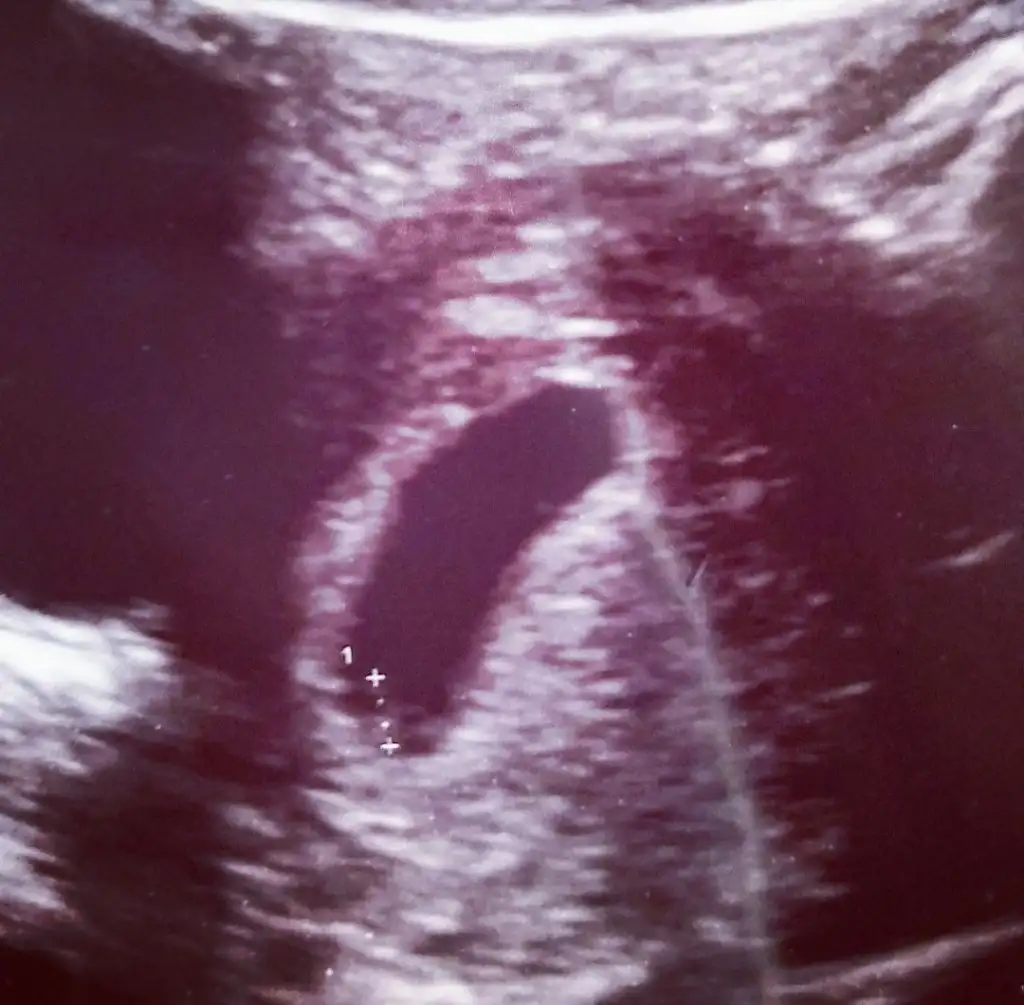

kızlar 6+3 buda benim fasulyem kesenin şekli hakkında yorumlarınızı merak ettiim keseye göre cinsiyet yorumu yapanlardan burdada var mıı